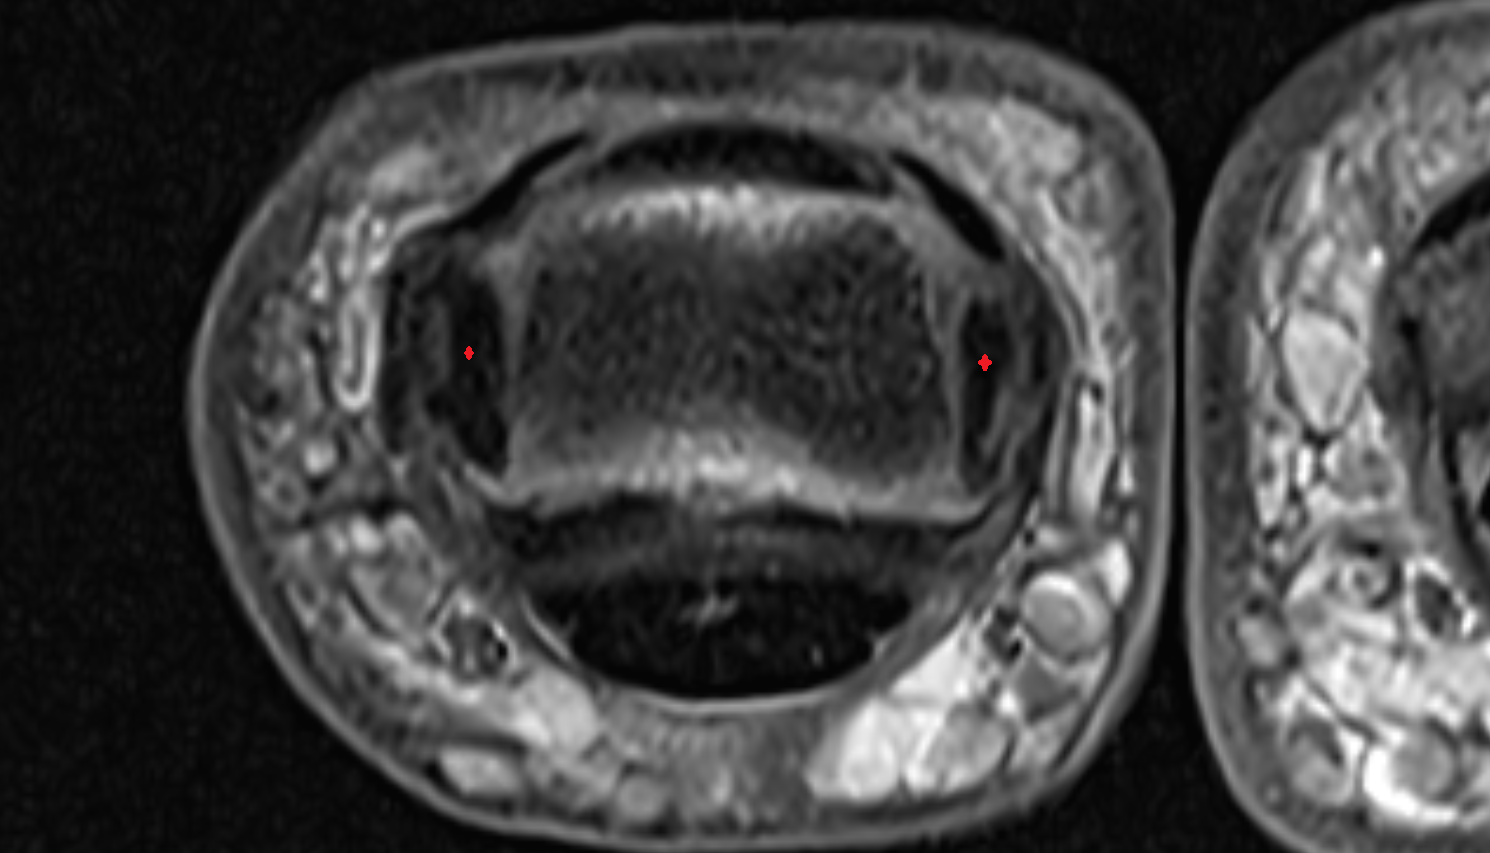

- Temporomandibular joint

- Mandibular condyle

- Mandibular fossa